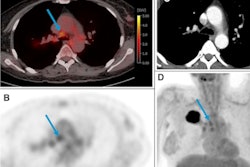

Zr-89 pembrolizumab-PET/CT image examples at day 7 of tumor lesions in various patients. Red arrows indicate tumor lesions. Images A and B are scaled 0-8 SUV, images C and D are scaled 0-5 SUV. A) Tumor lesion left upper lobe, NSCLC. B) Pulmonary metastasis, melanoma. C) Brain metastasis, melanoma (SUVmax 4.20). D) Abdominal wall metastasis, melanoma (SUVmax 5.02).In previous studies, the German group showed that the uptake of Zr-89 pembrolizumab-PET revealed tumors in mice. In this study, they sought to assess how effective it is in patients with melanoma and NSCLC.

The researchers recruited 18 patients with advanced or metastatic melanoma or NSCLC from two centers in the Netherlands. Patients first received Zr-89 pembrolizumab infusions and then up to three PET scans on days 2, 4, and 7. Tumor uptake of Zr-89 pembrolizumab was calculated as maximum standardized uptake value (SUVmax). Normal organ uptake was calculated as SUVmean and tumor response was assessed according to RECIST v1.1.

The study authors found the optimal dose of pembrolizumab was 5 mg, and the optimal time point for PET scanning was on day 7. The tumor SUVmax did not differ between melanoma and NSCLC (4.9 and 6.5, P = 0.49). In addition, tumor uptake of Zr-89 pembrolizumab correlated with tumor response (Ptrend = 0.014) and progression-free (p = 0.0025) and overall survival (p = 0.026), the researchers wrote.